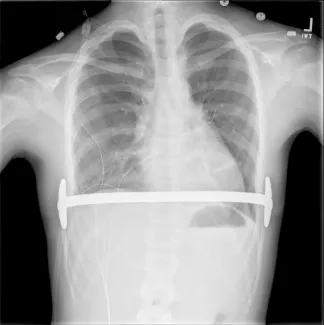

Repair with a metal pectus bar, called the Nuss Procedure, is achieved by bending a stainless bar to fit the chest wall. The bar is then inserted and secured through a small incision under each arm using the aid of a endoscope to monitor and avoid injury to the heart during insertion. The bar goes over the ribs and under the sternum, to push the sternum forward into the new position. The ends of the bar are secured to the chest wall. This procedure takes between 1–2 hours.

- Sports may be resumed as soon as the surgeon determines this is safe. Some contact sports may be not be permitted while the bar is in place. The bar may prevent adequate chest compressions during CPR and defibrillation requires paddle adjustment to be effective.

- No MRI should be done while the Pectus bar in in place.

- Use of a medical alert bracelet or necklace is recommended at all times in order to notify emergency providers of the presence of a Pectus bar. Recommended bracelet text: Steel bar in chest. CPR more force. Cardioversion ant/post paddle placement.